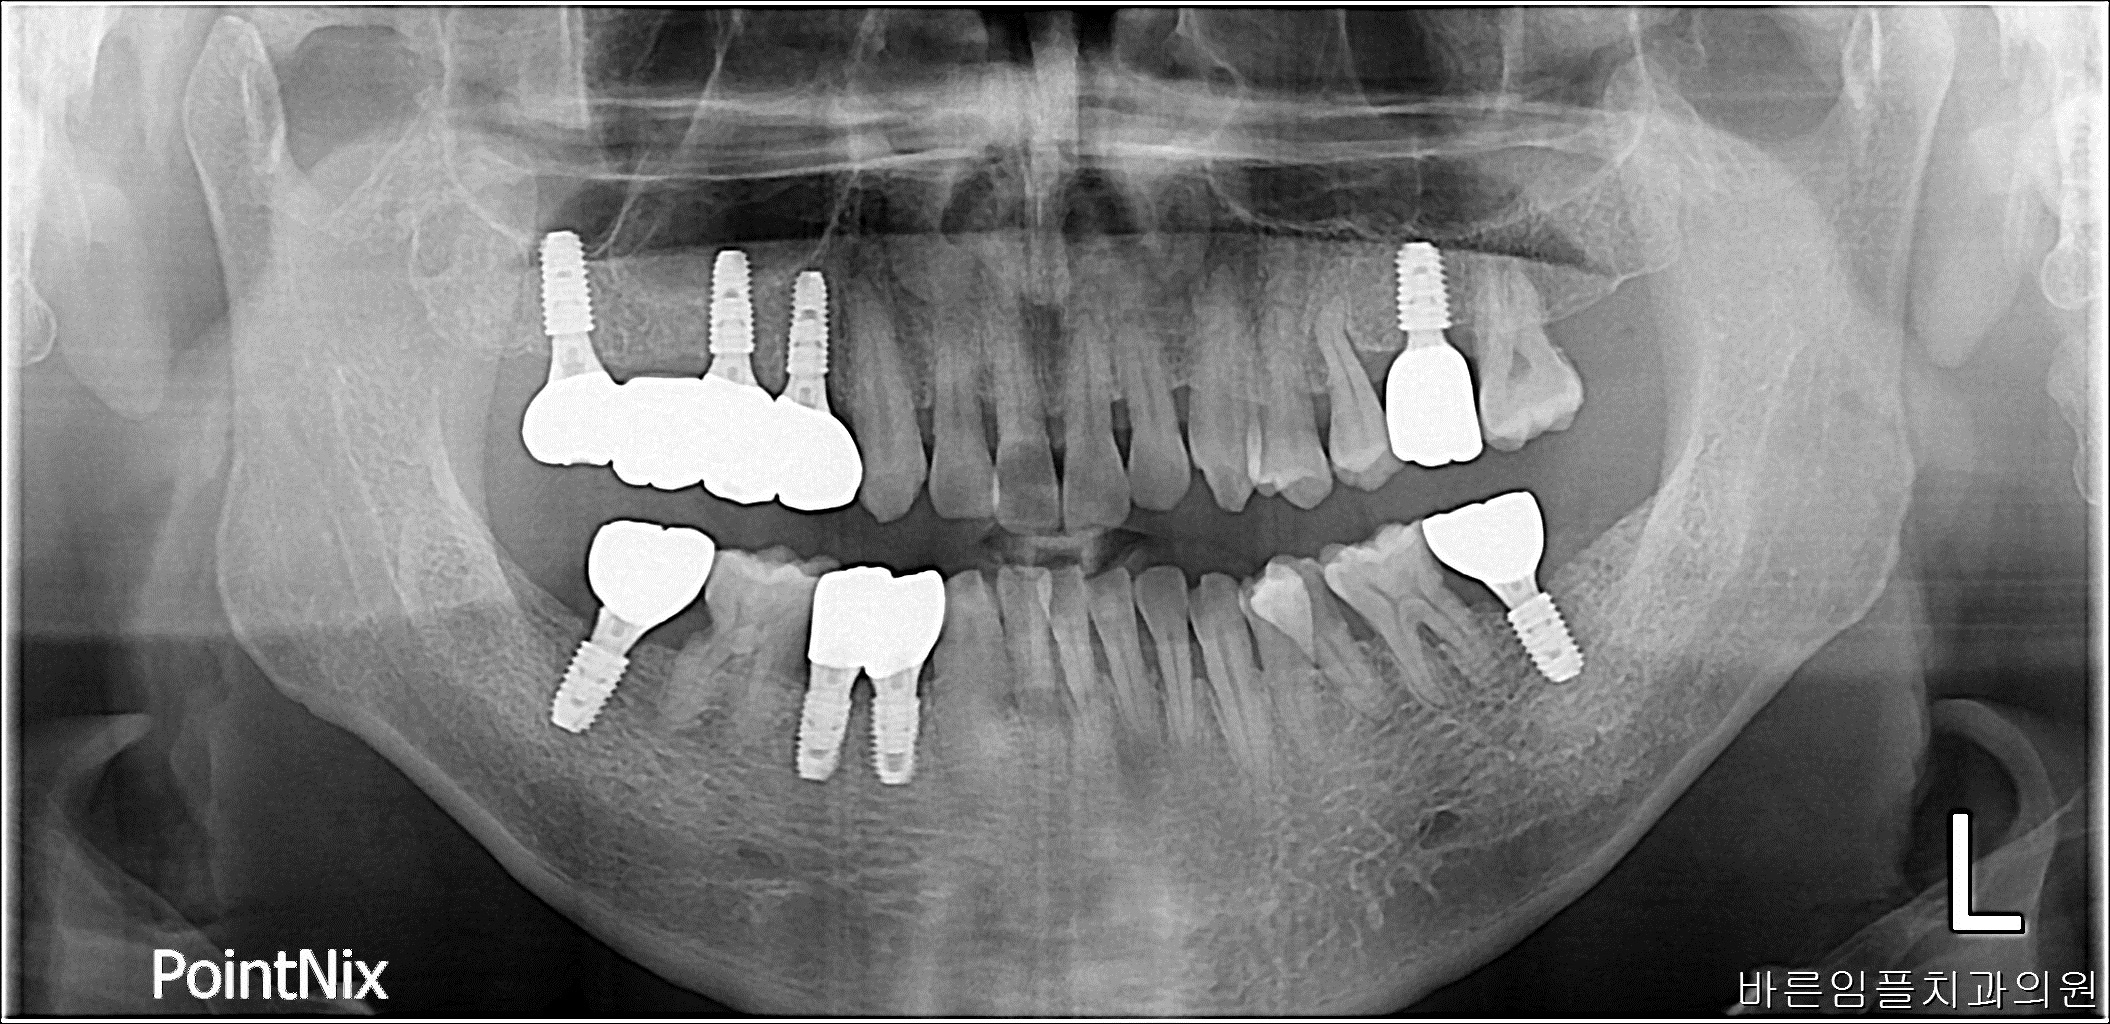

박ㅇㅇ / 수면임플란트 페이지 정보 작성일 23-10-27 17:02 2023-04-20 박ㅇㅇ Before 2023-09-07 박ㅇㅇ After 박ㅇㅇ / 수면임플란트 목록 이전글이ㅇㅇ / 수면임플란트 다음글 남ㅇㅇ / 임플란트